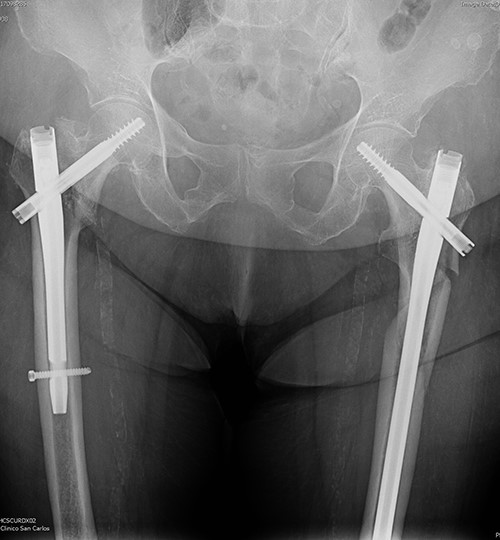

The postoperative course was satisfactory, without medical problems apart from non-complicated anemia (Hb 7.9 g/dl), solved with two units of red blood. On the first postoperative day, a radiographic control was completed (Fig. 3) and started early ambulation assisted by physiotherapists. On day twelve, she was transferred to a rehabilitation hospital. Outpatient follow-up visits evolving reasonably well. In the 6-month and 1-year check-up, the consolidation of the fracture was observed in the radiographic study (Fig. 4). No surgical wound problems, infections, or limping were identified. Anti-osteoporotic drug treatment was implemented along with an emphasis on a healthy diet with adequate protein intake and supplementation with calcium and vitamin D.

Postoperative anteroposterior pelvis radiograph: The left subtrochanteric fracture was first reduced with percutaneous assistance and synthesized with a reamed intramedullary long Gamma3 nail (340 mm,125°, Stryker®) with cephalic dynamic locking screw and two static distal locking screws. Then, after closed reduction, the right intertrochanteric fracture was fixated with a non-reamed short Gamma3 nail (180 mm,125°, Stryker®) with cephalic and distal dynamic locking screws.